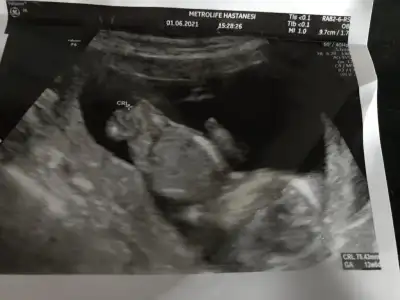

Kız görünüyorYenisi ekledim![]()

Doktorum da ilk böyle dedi pazartesi gttim kıza benzettim dediErkeğim diye bağırıyor![]()

Kız gibi sanki daha önceki karanlık USG emin olmamıştımBen bugün gene kontroldeydimIkra meyra her seferin farklı tahminde bulunuyor ama bugün met ve emin söyledi. Bakalım sen ne diyeceksin? Bemce poposu dönük ama öyle bişey demedi.

Evet bu sefer de kız dedi kesin konuştu ama ben 20. Hafta detaylıyı beklecepim emin olmak için. Teşekkür eserimKız gibi sanki daha önceki karanlık USG emin olmamıştım